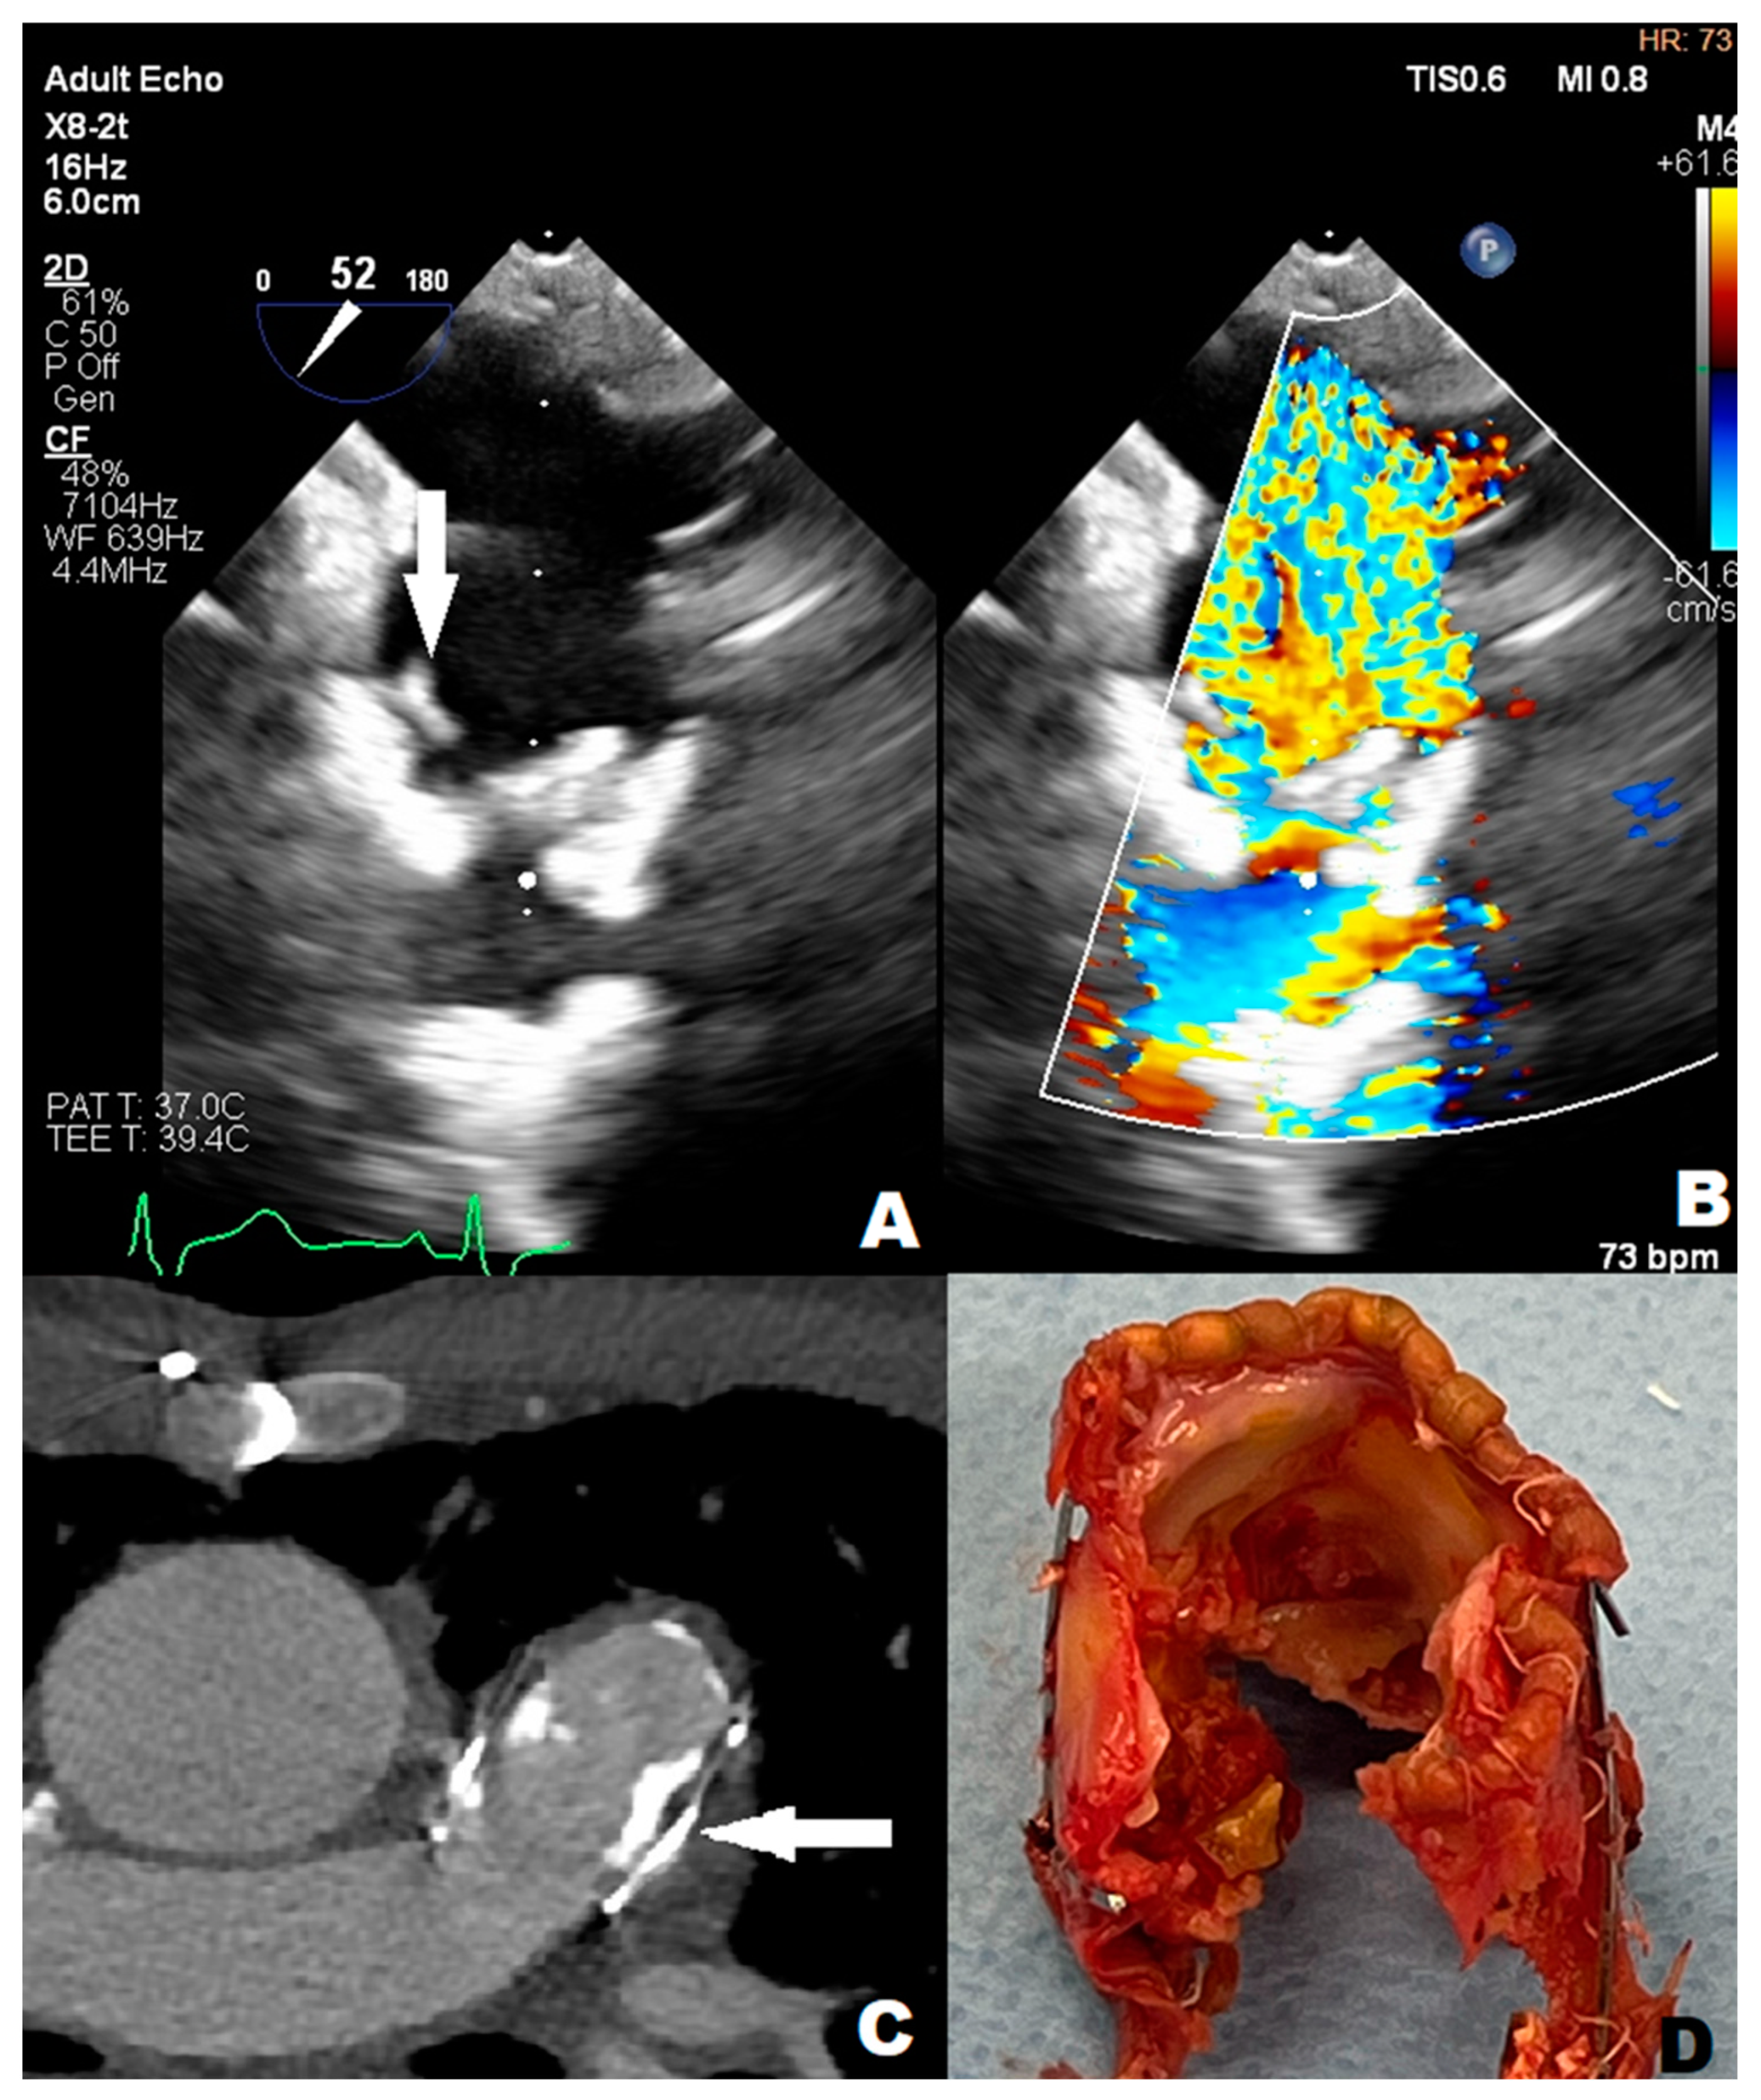

An 11-year-old boy was admitted to the emergency department with a 40 degrees Celsius fever and mycotic lesions in the oral mucosa. Previously, the boy had undergone the following procedures: complete repair of Tetralogy of Fallot (ToF) and right pulmonary artery balloon angioplasty during infancy, BioPulmonic 21 biological valve implantation in the pulmonary valve (PV) position at the age of two, and left pulmonary artery reconstruction and balloon angioplasty one year after the reconstruction. The boy did not present other infectious symptoms and his health state was stable. The systolic heart murmur was 4/6 on the Levine Scale (LS). The patient did not present any other symptoms in the physical examination. A series of laboratory blood tests were performed, and the following results were slightly elevated: C-reactive protein (6.30 mg/L) (CRP), procalcitonin (0.10 ng/mL) (PCT), other inflammation indicators, N-terminal pro-b-type natriuretic peptide (319.7 pg/mL) (NT-proBNP), and troponin. The reference ranges of the laboratory tests are provided in the Supplementary Material (Table S1). The inflammatory and congestive changes were present on the chest X-ray. The blood culture samples were taken according to the ESC procedure, which involves obtaining three sets of 10 mL blood samples from peripheral veins at 30 min intervals before initiating antibiotic therapy. Ceftriaxone (2 g/day) and vancomycin were administered empirically for treatment. A few days later, ceftriaxone-sensitive Kingella Kingae (KK) was detected; HACEK group bacteria were isolated from two sets of blood culture samples. The boy was transferred to an upper reference department where ceftriaxone therapy was continued. The TTE examination showed that the right ventricle (RV) was hypertrophied and dilated and the PV flow was turbulent with max PG 120 mmHg with moderate PV regurgitation, without any vegetations. However, the transesophageal echocardiography (TOE) showed numerous, slightly built, ballotable vegetations (Figure 1A,B). The PV cuspids were difficult to see because of the BioPulmonic metal frame and numerous calcifications in the angio-CT (Figure 1C). In summary, the patient met three major criteria and one minor Duke’s criterion, confirming the definite nature of the IE. During the whole period of hospitalization, the boy felt well, the inflammation indicators decreased, and blood culture results became negative, but NT-proBNP (319.7 pg/mL) was still subtly elevated. After the full 6-week treatment, the boy was qualified for PV replacement surgery (Figure 1D). He left the Cardiac Surgery Department in a state of maximum improvement. The patient still remains under outpatient cardiological care.

Figure 1.

(A) arrow point at slightly-built, ballotable vegetation well-visible in TOE (B) BioPulmonic regurgitation wave in TOE; (C) arrow point at BioPulmonic metal frame visible in angio-CT; (D) the BioPulmonic PV after cardiac surgery; TOE—transesophageal echocardiography; angio-CT—angio computed tomography.